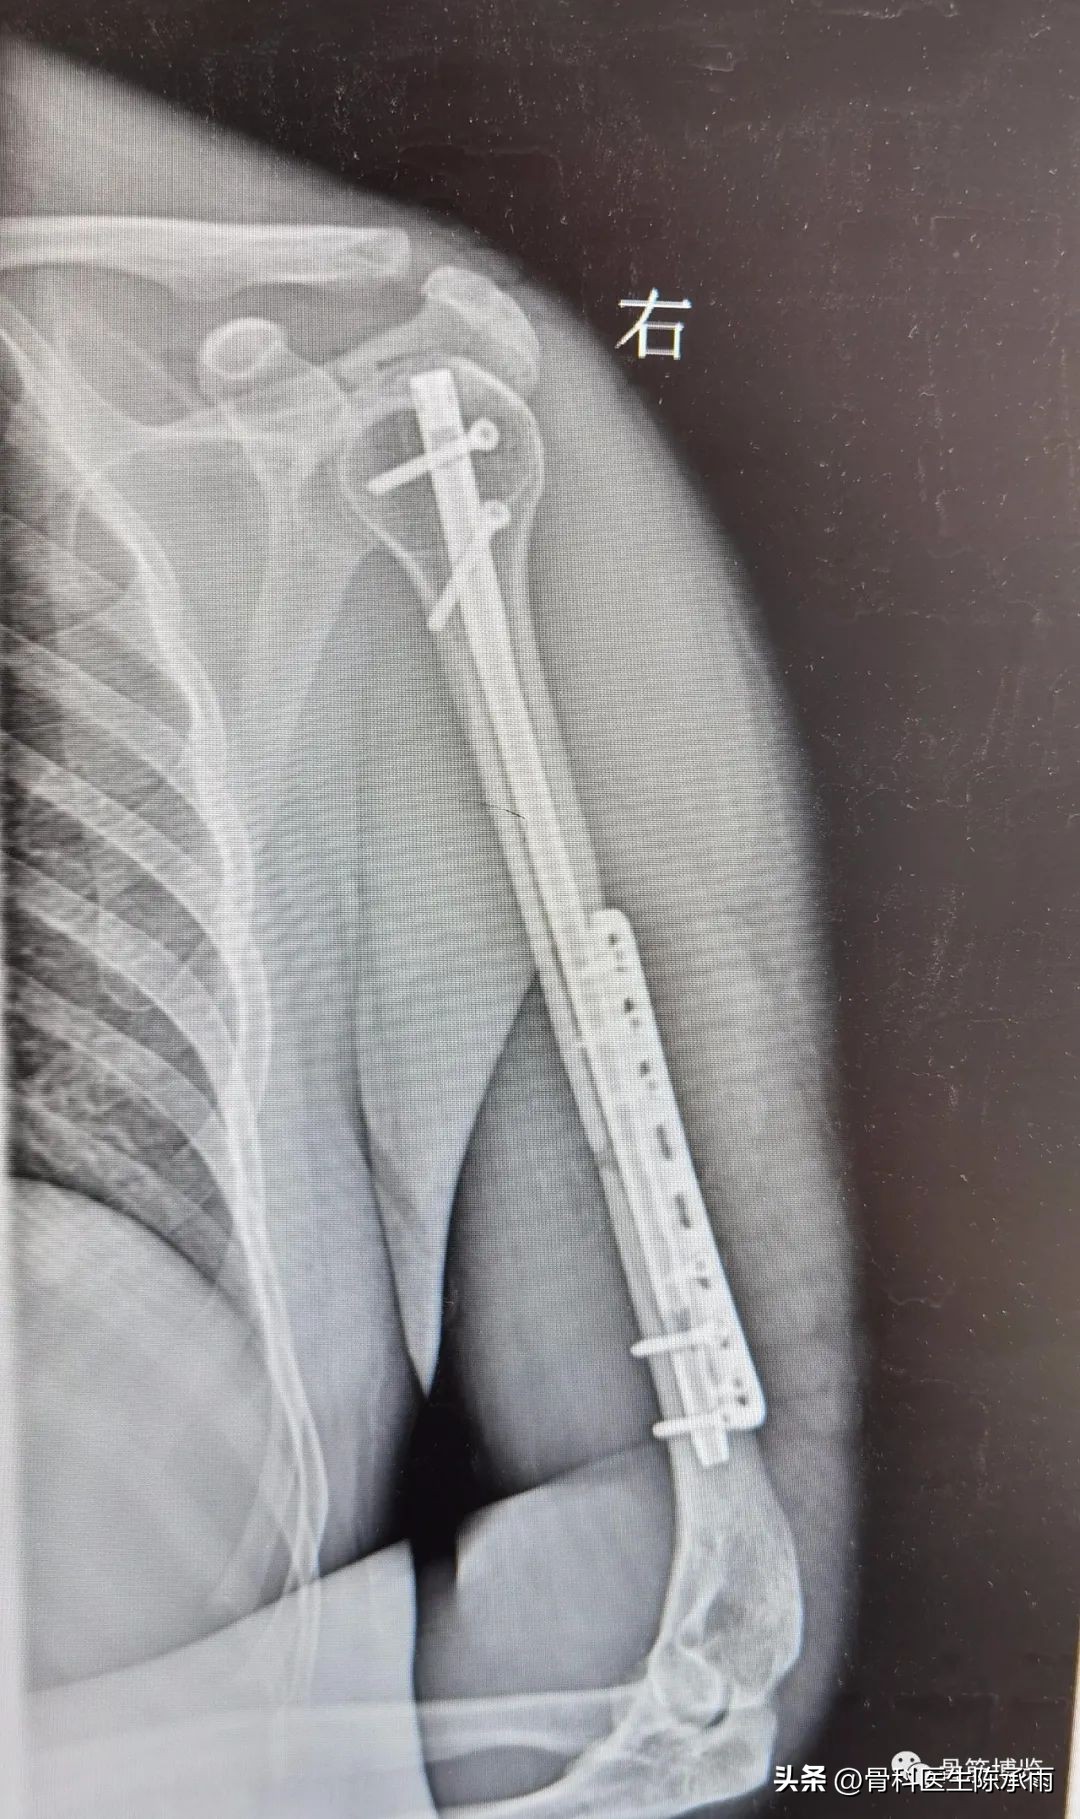

Shoulder Fracture Screws . If you need surgery, the doctor will fix your bone with metal plates and screws. Penn orthopaedic specialists treat every type of shoulder fracture using the latest diagnostic and treatment techniques that offer the best possible outcomes. If your shoulder is in many pieces, the doctor might recommend a shoulder replacement instead. Shoulder fractures most often involve the clavicle (collarbone), proximal humerus (top of the upper arm bone), or the scapula (shoulder blade). The options for surgery include realigning the bone fragments and holding them in position with metal implants, or a shoulder replacement procedure is performed. Shoulder dislocations can involve any of. Treatment for these fractures can vary. During the procedure, the bone fragments are repositioned into their normal alignment, and are. A shoulder fracture repair may include plates and screws as shown here. Simple sling or “figure 8” strap worn for three to eight. Internal fixation is a surgical procedure used to internally set and stabilize fractured bones.

Humeral Shaft Fracture Fixation Shoulder Surgeon South Windsor Shoulder Fracture Screws During the procedure, the bone fragments are repositioned into their normal alignment, and are. Simple sling or “figure 8” strap worn for three to eight. If you need surgery, the doctor will fix your bone with metal plates and screws. The options for surgery include realigning the bone fragments and holding them in position with metal implants, or a shoulder. Shoulder Fracture Screws.

Internal fixation of humerus fractures with interlocking screws iNEWS Shoulder Fracture Screws Treatment for these fractures can vary. A shoulder fracture repair may include plates and screws as shown here. If your shoulder is in many pieces, the doctor might recommend a shoulder replacement instead. During the procedure, the bone fragments are repositioned into their normal alignment, and are. Internal fixation is a surgical procedure used to internally set and stabilize fractured. Shoulder Fracture Screws.